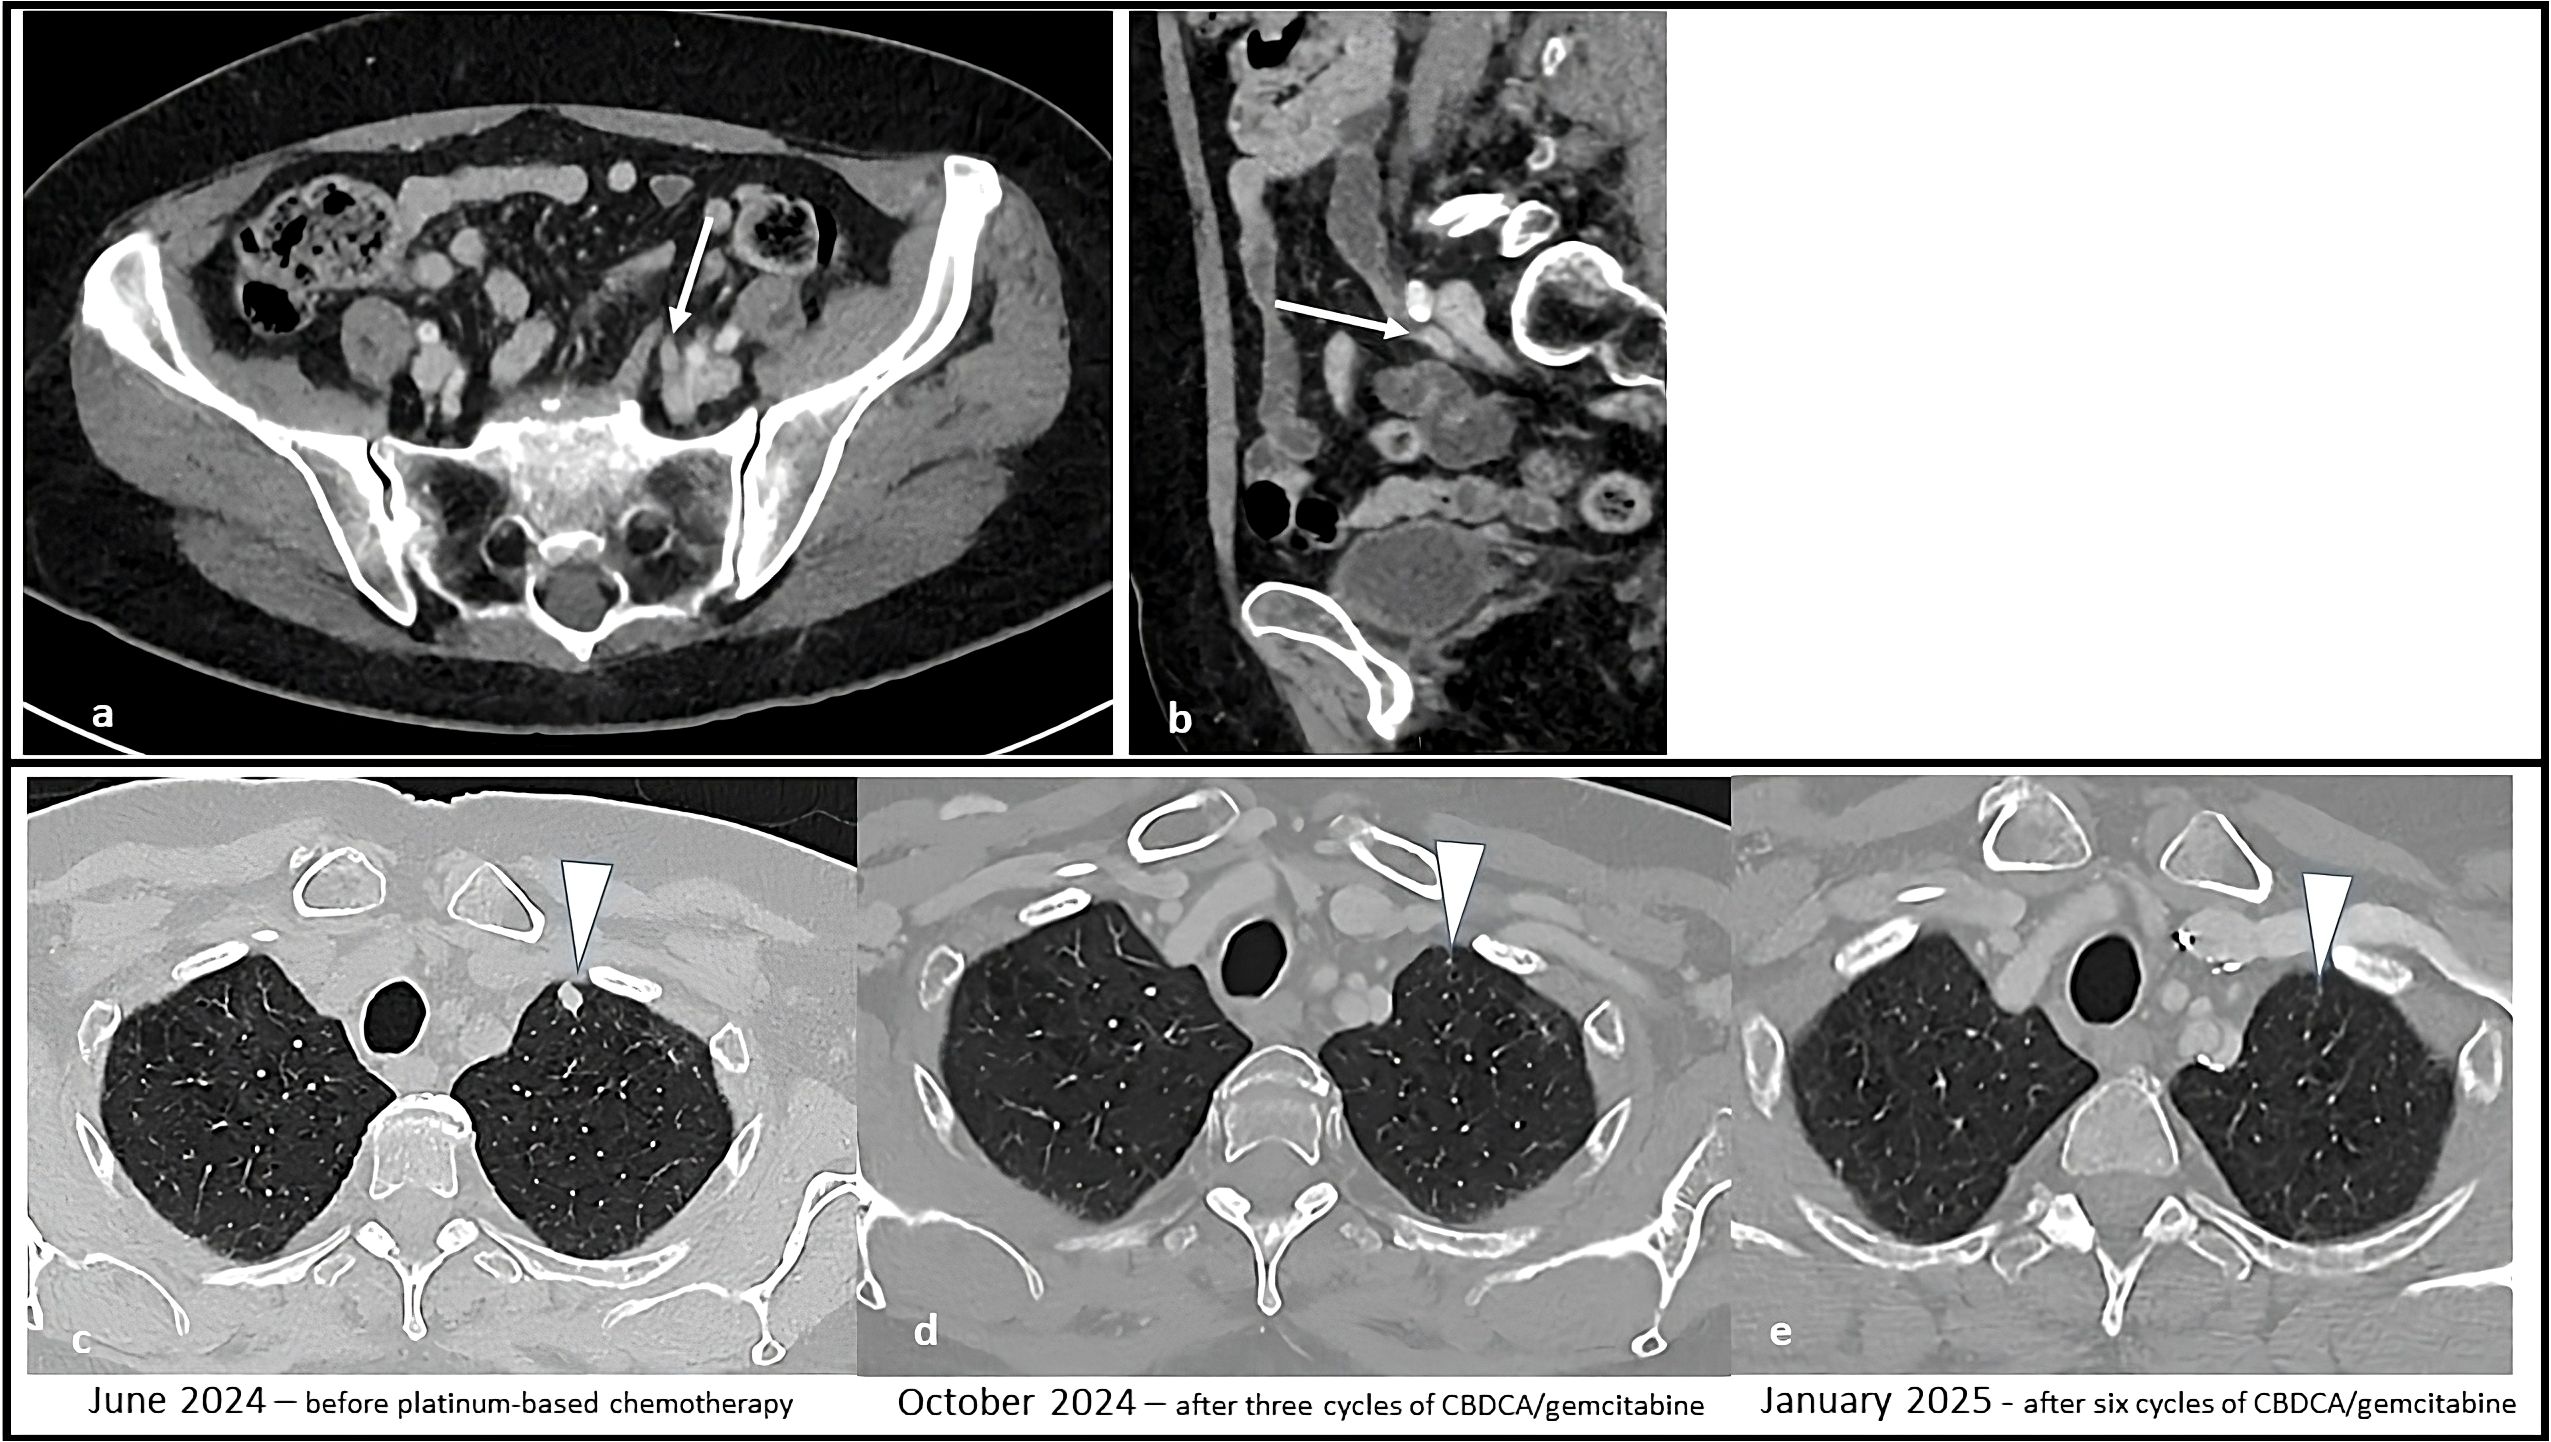

Figure 3

CT scan images showing treatment progress over time. Image a displays a cross-sectional abdominal view, with an arrow indicating a specific area. Image b shows a sagittal view highlighting another region with an arrow. The bottom row includes three thoracic scans labeled June 2024, October 2024, and January 2025, marking stages before and after chemotherapy cycles. Arrows point to a focus area in each scan, demonstrating changes in response to treatment.

Figure 3. Sequential CT scans showing disease progression during treatment with enfortumab vedotin plus pembrolizumab and subsequent partial response with platinum-based chemotherapy. Solid tissue within the left ureter causing hydronephrosis (white arrow) in the axial (a) and sagittal (b) CT images. Afterwards, the appearance of solid lung nodules was noted [white arrowhead in (c)], that progressively responded to therapy (d) and disappeared (e).

A CT scan performed after four cycles (March 26, 2024) showed stable disease per RECIST 1.1, with minimal reduction in the left supraclavicular. However, a follow-up CT scan five months after treatment initiation (June 2024, after 8 cycles of EV and 4 cycles of P) revealed multiple new suspicious millimetric pulmonary nodules. A confirmatory CT imaging performed one month later confirmed disease progression (Figure 3).

EV treatment was discontinued and second-line chemotherapy with carboplatin AUC 5 plus gemcitabine 1000 mg/m² was initiated in August 2024. Carboplatin was chosen because of a mildly reduced glomerular filtration rate of 45 mL/min/1.73 m2. From the third cycle onwards, both drugs were administered at a 25% reduced dosage because of emergent grade 3 thrombocytopenia and neutropenia. A CT scan after three cycles (October 31, 2024) showed a partial response according to RECIST 1.1., with both numerical and dimensional reduction of the pulmonary nodules. The case was subsequently discussed at our multidisciplinary board which, due to the good response to treatment, suggested continuing treatment with carboplatin plus gemcitabine for up to six cycles. After the completion of six chemotherapy cycles (January 2025) the patient repeated a CT staging which showed a further reduction in lung nodules (Figure 3). A follow-up CT scan performed in March 2025 showed no sign of disease progression.